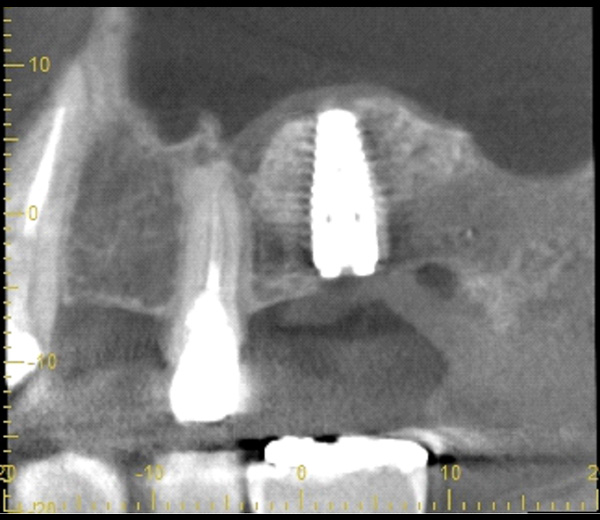

| 年代・性別 | 50代 男性 |

|---|---|

| 主訴 | 前医で前歯を抜かなければならないがインプラントはできないと言われた |

| 治療期間 | 約12ヶ月 |

| 費用 | 600,000円 |

| 治療内容 | インプラント、骨造成、結合組織移植、セラミック修復 |

| 治療に伴うリスク | インプラント周囲炎 セラミックの破折、脱離 |